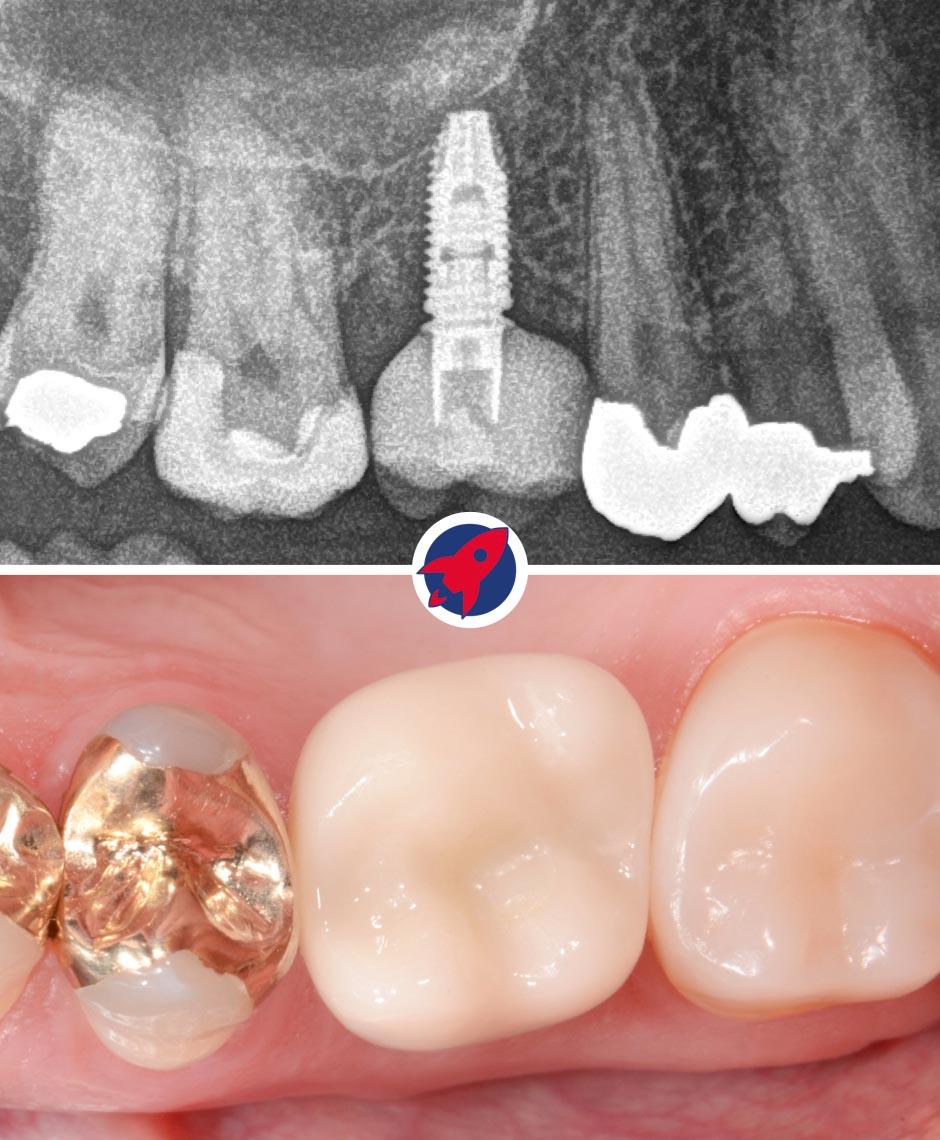

Oben sehen Sie ein Röntgenbild, das das Implantat mit aufgesetzter Zahnkrone zeigt. Unten ist die Krone in der klinischen Ansicht im Mund dargestellt.

Endgültige Ansicht eines Zahnimplantats mit Krone: Hier ist das finale Ergebnis einer Implantatbehandlung zu sehen, bei dem das Implantat vollständig im Kiefer integriert ist und mit einer individuell angefertigten Zahnkrone abgeschlossen wird, die sich nahtlos in die natürliche Zahnreihe einfügt.